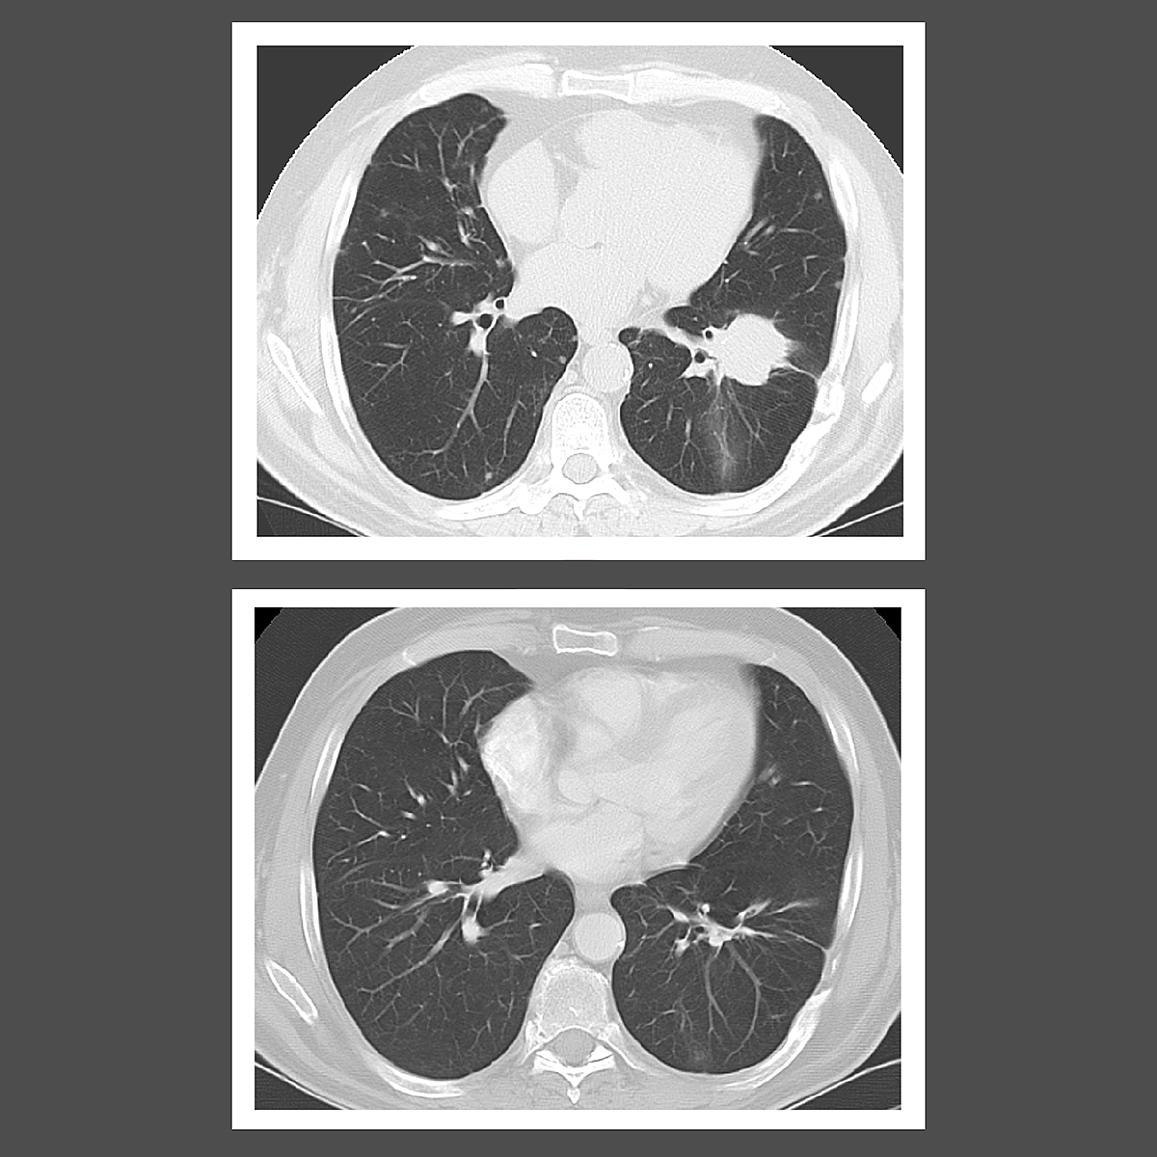

Results from a clinical trial conducted by researchers at the National Institutes of Health (NIH) show that people with low-grade lymphomatoid granulomatosis who are treated with interferon alfa-2b, a type of immunotherapy, can live for decades after diagnosis. Lymphomatoid granulomatosis is a rare precancerous condition triggered by Epstein-Barr virus infection. Left untreated, the disease can progress to a high-grade form, which has a poorer prognosis and can quickly turn into an aggressive and fatal B-cell lymphoma.

In the phase 2 trial, led by researchers in the Center for Cancer Research at the National Cancer Institute (NCI), part of NIH, patients treated with interferon alfa-2b lived for a median of about 20 years. By contrast, past studies reported a median survival of less than two years for people with lymphomatoid granulomatosis.

The findings suggest that immunotherapy can prevent the progression of low-grade disease to high-grade disease. The results were published March 31, 2023, in Lancet Haematology.